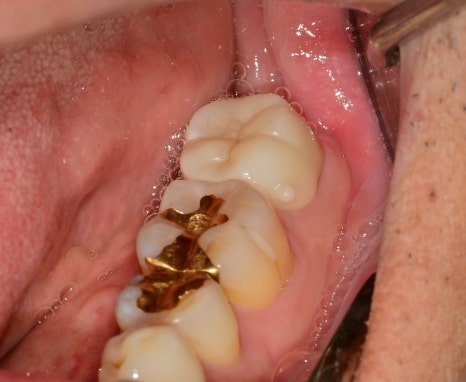

치아를 보강하고 그 위에 크라운 치료까지 마무리되었습니다.

과거에 때웠던 치아에 약한 재료가 파절되면서

그 안쪽으로 충치가 진행되면서 신경관 입구가 노출되며 MTA 적용 후 레진 보강 후

크라운치료로 같은 과정으로 치료가 마무리된 케이스입니다.